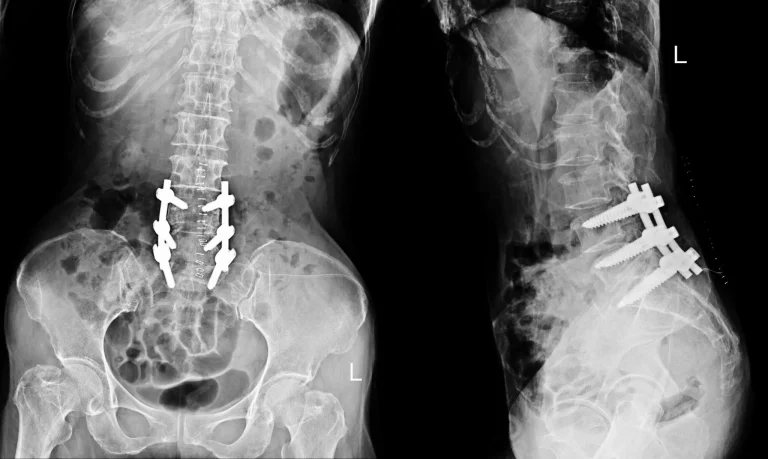

X-ray showing spinal hardware in the lower back from front and side views.

Additional Surgery Necessary